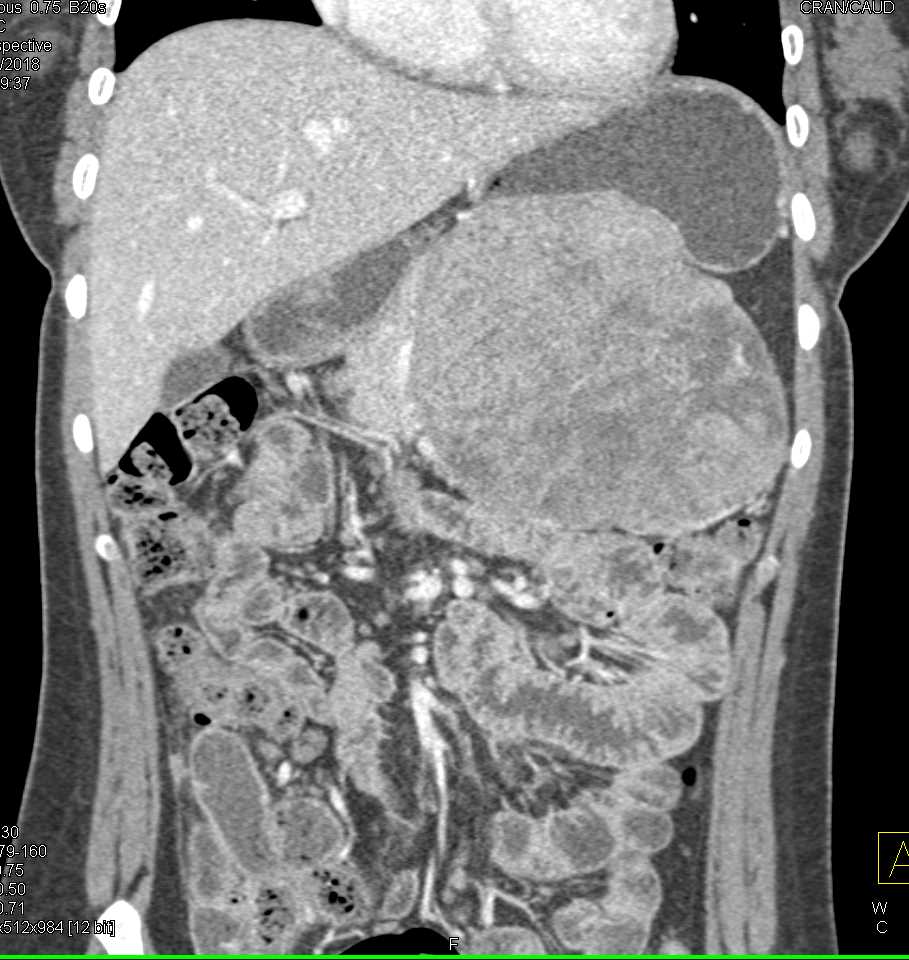

Gastric GIST Tumor